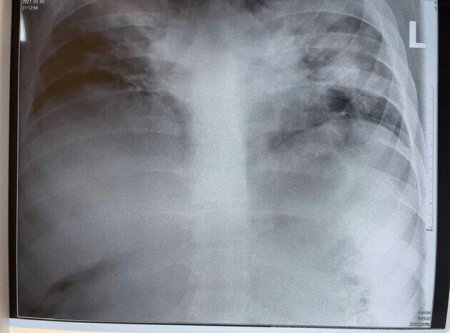

"COVID-19" помолодшав ", збільшилася кількість пацієнтів не тільки 30+, а й молодші. На фото - рентгенограма 18-річного молодого чоловіка без явної супутньої патології", - написала вона.

За її словами змінилася ефективність терапії і перебіг хвороби. На даному етапі, медики намагаються адаптувати наукові підходи до лікування важких хворих, виходячи з нових умов.